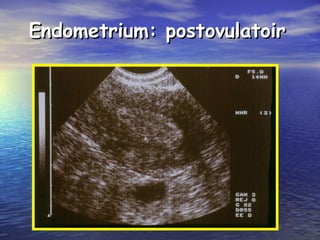

Endometrium: postovulatoirEndometrium: postovulatoir